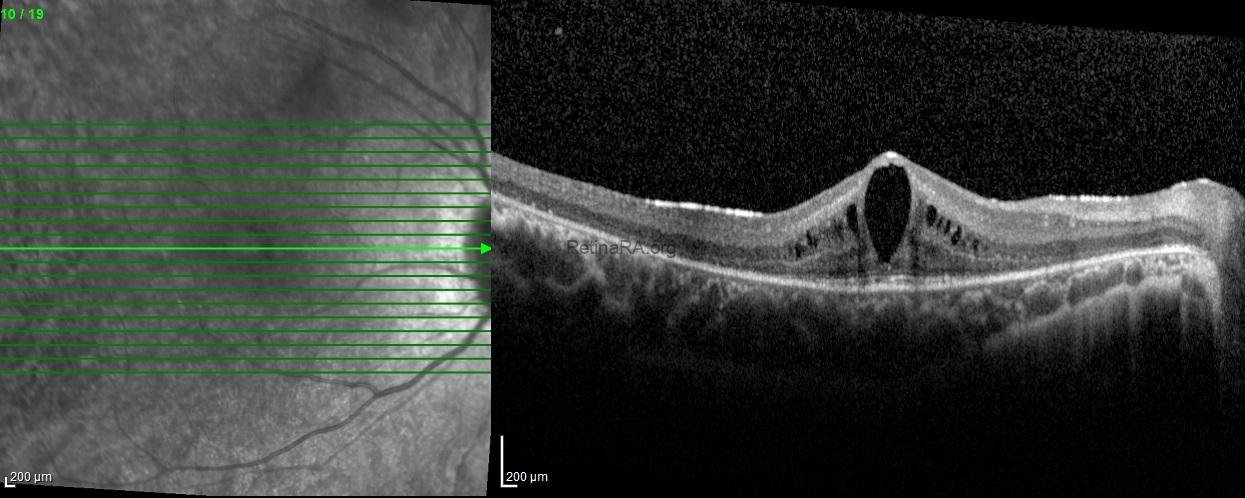

Optical coherence tomography scans revealed decreased thickness of the outer nuclear layer, along with loss of the external limiting membrane and ellipsoid zone in both eyes, sparing the fovea. Hyporeflective cystoid spaces were also observed in both eyes.

A clinical diagnosis of Usher syndrome was made based on the history (poor night vision and hearing impairment since childhood), clinical findings (peripheral vision loss, mid-peripheral bony spicules, and arteriolar attenuation), and investigative results (optical coherence tomography, electroretinography, and pure tone audiometry).

Usher syndrome is an autosomal recessive disorder combining congenital sensorineural hearing loss with progressive retinal degeneration (retinitis pigmentosa). Fundus findings typically include bone spicule pigmentation, arteriolar attenuation, and optic disc pallor. Optical coherence tomography often reveals thinning of the outer retinal layers with loss of the ellipsoid zone, sparing the fovea in early stages. Full-field electroretinography demonstrates markedly reduced or extinguished scotopic and photopic responses. Early recognition allows appropriate genetic counseling, auditory rehabilitation, and multidisciplinary management.